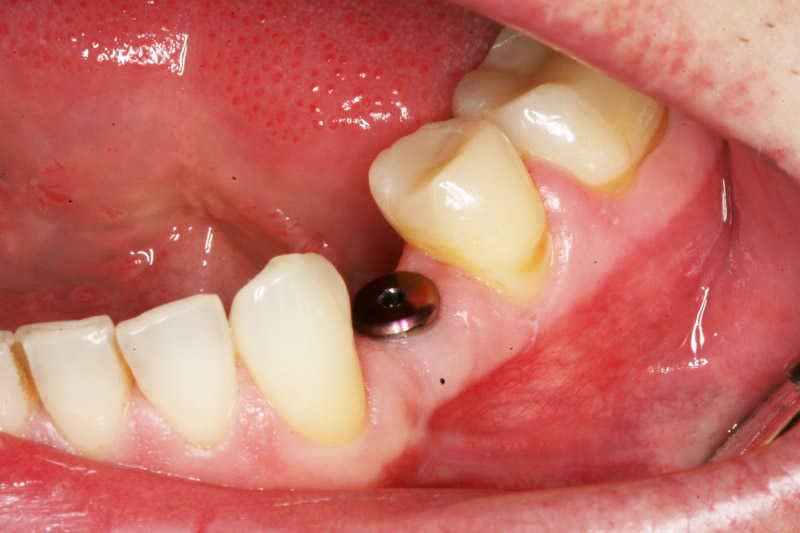

2

Az implantátum megkapta a végleges titán koronatartó fejet